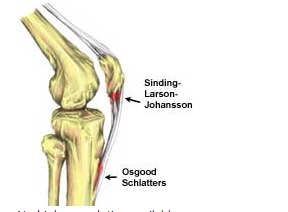

슬패골밑에 있는 경골조면에서만 통증이 나타나고 강합 압통이 주 증상 입니다. 국소적인 열감과 함께 붓는 느낌이 들면서 뼈가 튀어나온 것을 확인할 수 있습니다.

무릎 앞쪽 약간 아래가 아프고 부으면서 무릎 아래에서 뼈가 돌출되는 것이 보인다면 오스굿씨 병 의심해 볼 수 있습니다.

X-ray 검사를 합니다. 성장단계에 따라 크기는 다르지만 경골조면 즉 무릎의 바로 아래에 국한된 골단핵 변화, 유리골편이라는 것이 보여집니다. MRI검사를 하면 연골부를 덮고 있는 슬개건이 두꺼워져 있거나 주변 염증성 변화를 확인할 수 있습니다. 초음파로도 돌출된 뼈와 인대 비후도 볼 수 있습니다.